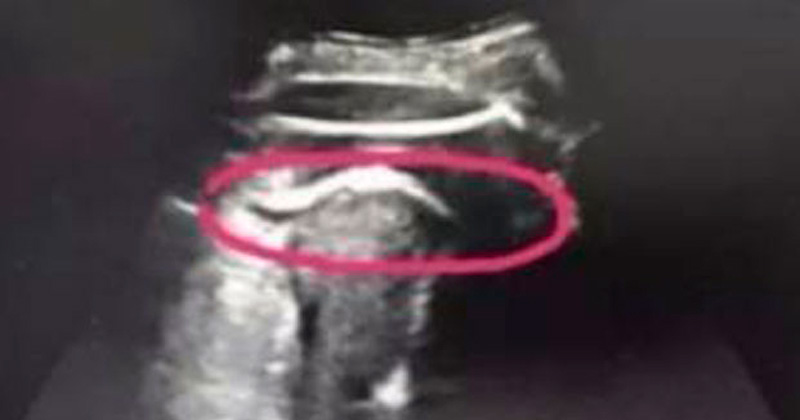

Bebé casi mata a su madre de una patada

Una mujer con 35 semanas de embarazo estuvo a punto de perder la vida ya que su bebé pateó muy fuerte su útero